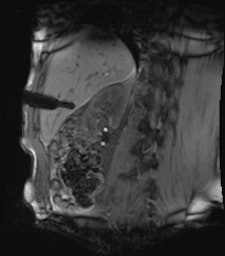

All procedures were performed using a wide-bore 1.5-tesla MR system (Magnetom Espree, Siemens Healthcare). A radiofrequency-shielded liquid-crystal display monitor was installed next to the magnet for real-time monitoring. During the procedures, imaging was performed with the use of a flexible four-channel body-array surface coil and a loop coil, and biopsies were performed with MR-compatible puncture needles. To obtain the specimen, an MR-compatible biopsy device (MRI Biopsy Handy, Somatex Medical Technologies) was used in 36 cases. After placing the MRI-compatible puncture needle in the magnet, two intramuscular biopsies were performed using a non-MR-compatible spring-loaded biopsy gun (ASAP, Boston Scientific) outside the magnet. During the biopsy, vital parameters were monitored using an MR-compatible patient monitor (Invivo 4500 MRI, Invivo Research).

In nine cases -- eight soft-tissue, one liver -- MR fluoroscopy was used to define the entry site, and the physician used a fingertip or water-filled syringe as a marker. In 29 cases -- 11 soft-tissue, 18 liver -- a marker capsule (Adalat, Bayer) was affixed to the supposed entry side with adhesive tape, and the position was corrected after application of conventional sequences. After sterile draping, administration of local anesthesia and skin incision, an MR-compatible puncture needle (14-18 G) was placed subcutaneously outside the magnet.